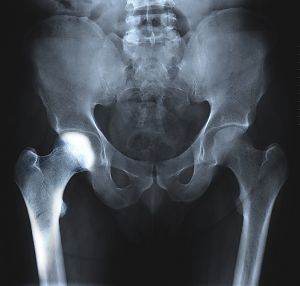

The hip joint is a ball-and-socket joint. A part of the pelvis bone known as the acetabulum forms the socket and the upper end of the femur, known as the femoral head, forms the ball.

You will also be recommended to undergo imaging studies such as X-rays, CT scans, MRIs, or nuclear scans to further document transient osteoporosis of your hip.